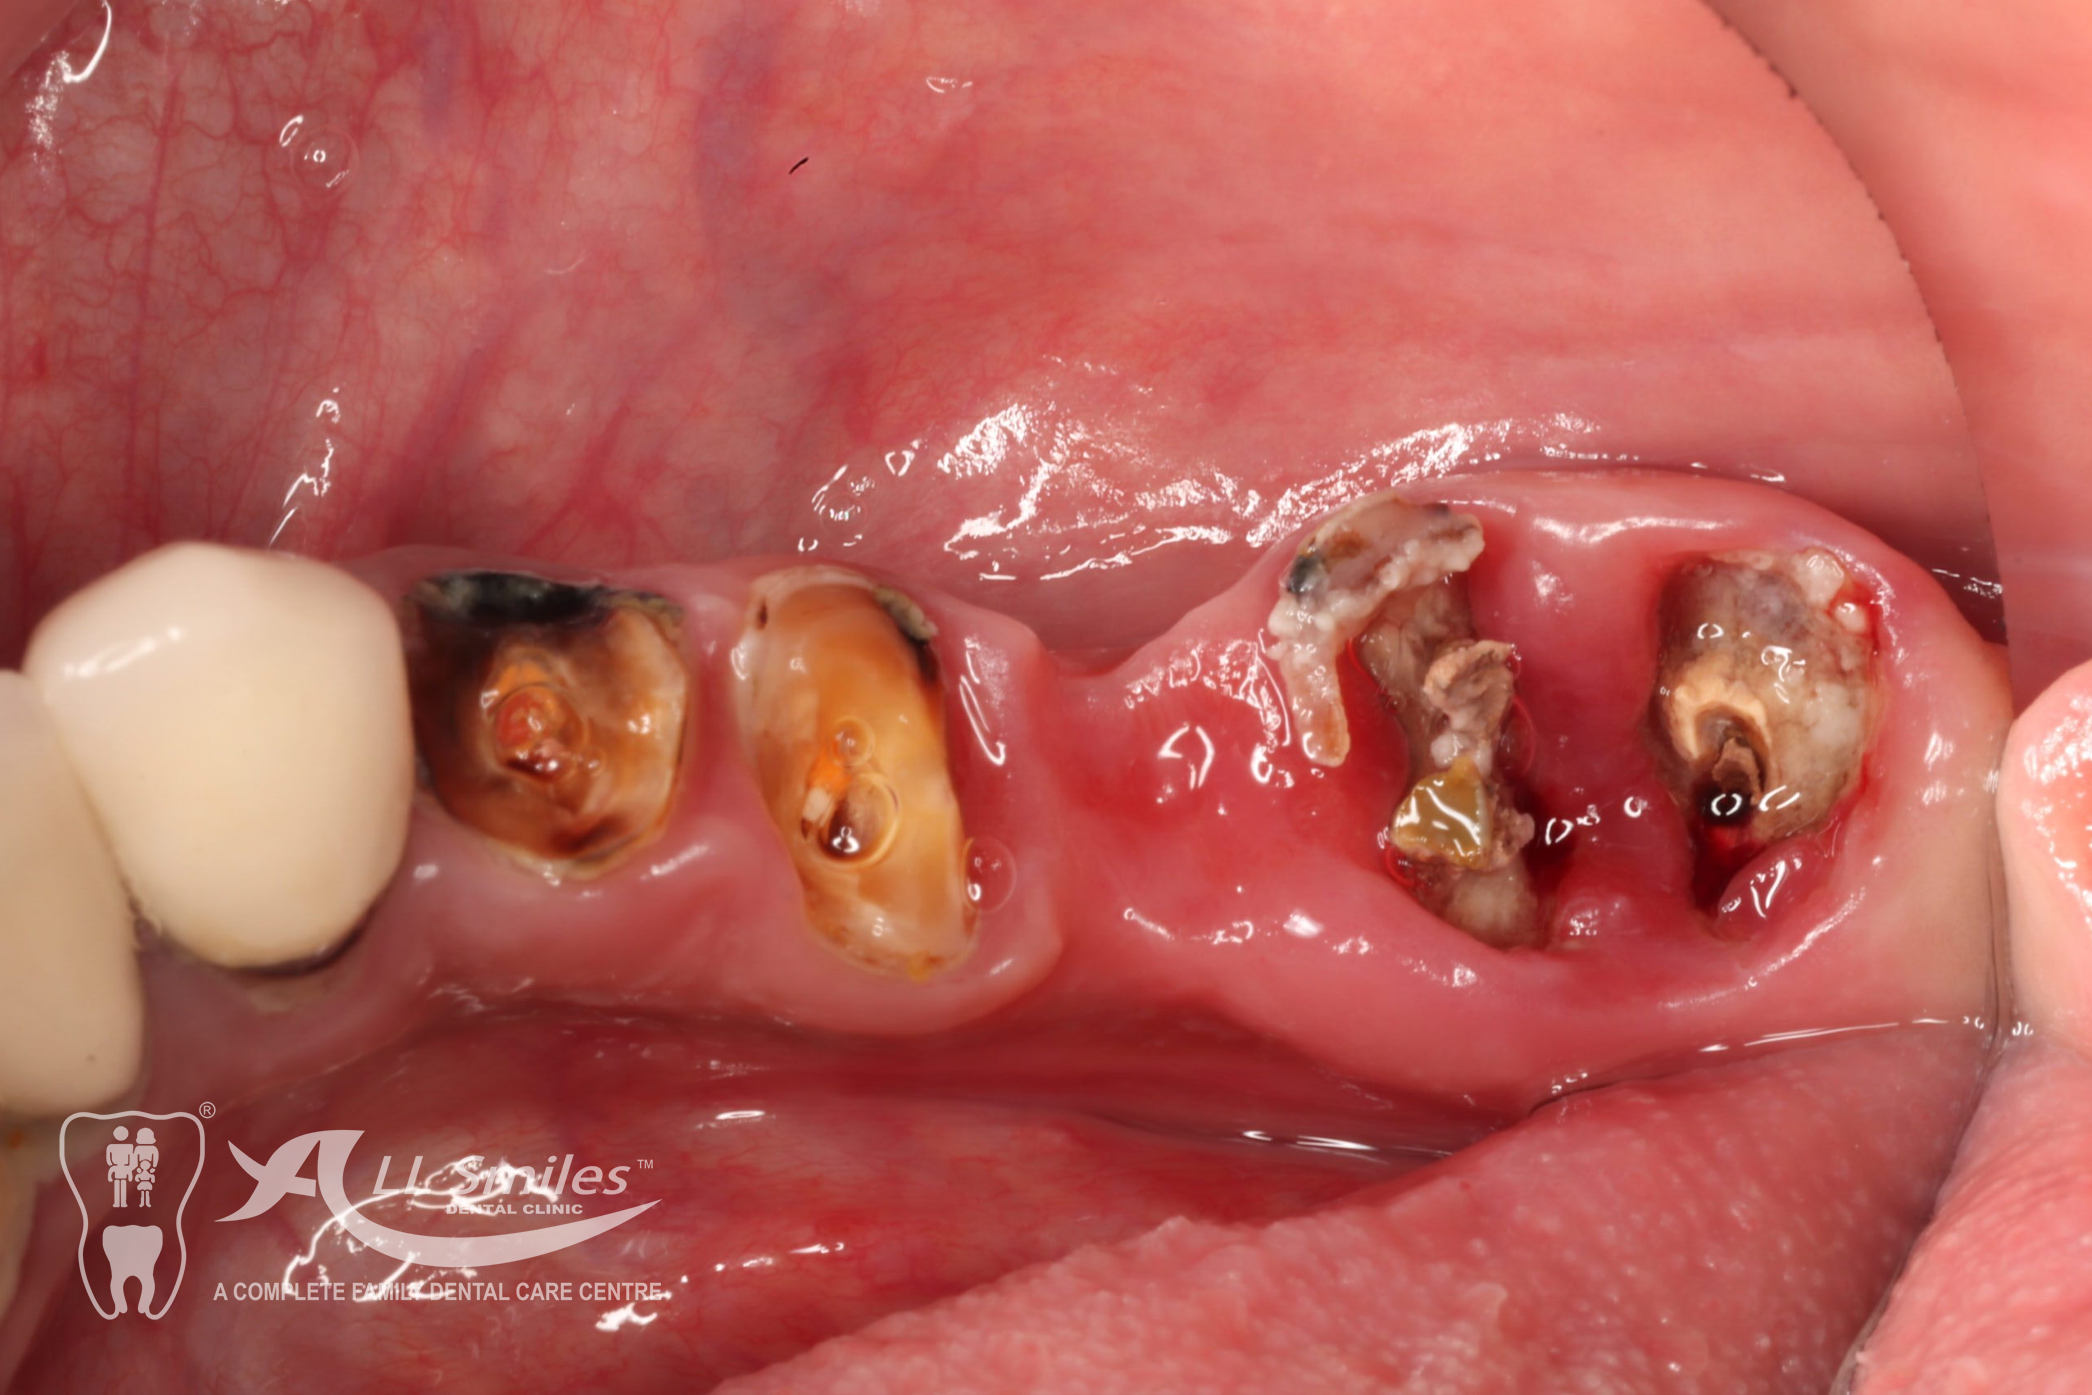

Implants For Multiple Missing or Broken Teeth Regardless of whether one or more teeth are missing in a row: Every tooth is individually replaced and the situation is restored to its original condition. If three or more teeth in a row are missing, you can decide to have an implant- borne bridge. In this solution the new crowns are linked together and depending on the size of the gap are placed on a stable and secure base of two or more implants .

After precise planning the new tooth roots are generally placed in the jaw in one single treatment session. A temporary denture closes the gaps during the healing phase. After healing the final crowns or the bridge are permanently fixed to the implants. Life With Bite! Dental Implants For The Edentulous Jaw.